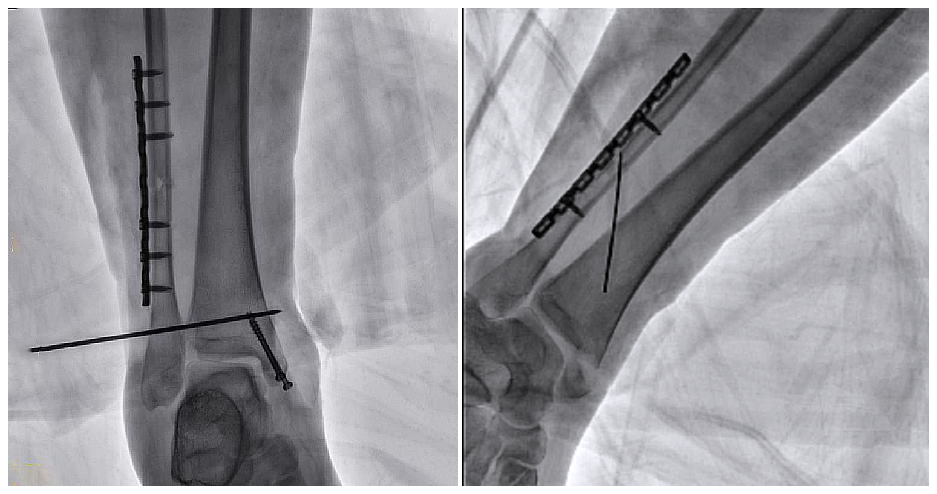

病例2 踝關節骨折復位(31歲)

在踝關節骨折復位手術中,用三維C可以更好地觀察骨折部位的復位情況:

正側位影像觀察脛腓聯合復位良好

從三維影像看,復位欠佳,貼合度不夠